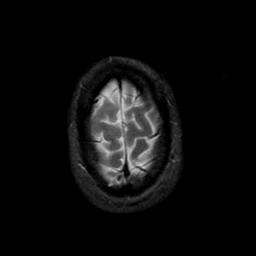

MR Study #21, November 3, 1991 -- Slice #45

[Home][Help][Clinical][Tour 1][Tour 2] Slice 45